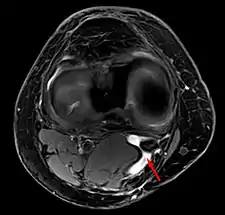

Diagnosis is by examination. A Baker's cyst is easier to see from behind with the patient standing with knees fully extended. It is most easily palpated (felt) with the knee partially flexed. Diagnosis is confirmed by ultrasonography, although if needed and there is no suspicion of a popliteal artery aneurysm then aspiration of synovial fluid from the cyst may be undertaken with care. An MRI image can reveal presence of a Baker's cyst.